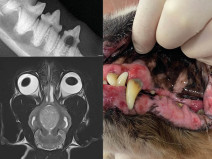

• Les Ateliers du Sud-Est : Autour de la tête

Les Ateliers du Sud-Est abordent cette année, du 6 au 8 octobre à Grasse, le thème transversal des affections pouvant atteindre la tête.

De nombreuses spécialités (dentisterie, cancérologie, ophtalmologie, dermatologie, neurologie, médecine interne, chirurgie et imagerie) seront ainsi abordées lors de trois pleines journées de conférences...

Du 6 au 8 octobre 2022

Grasse (06130)

Chirurgie

Dermatologie

Imagerie Médicale

Médecine Interne

Neurologie

Dentisterie-Stomatologie

Oncologie

Ophtalmologie

Pneumologie

Sud-Est

1234